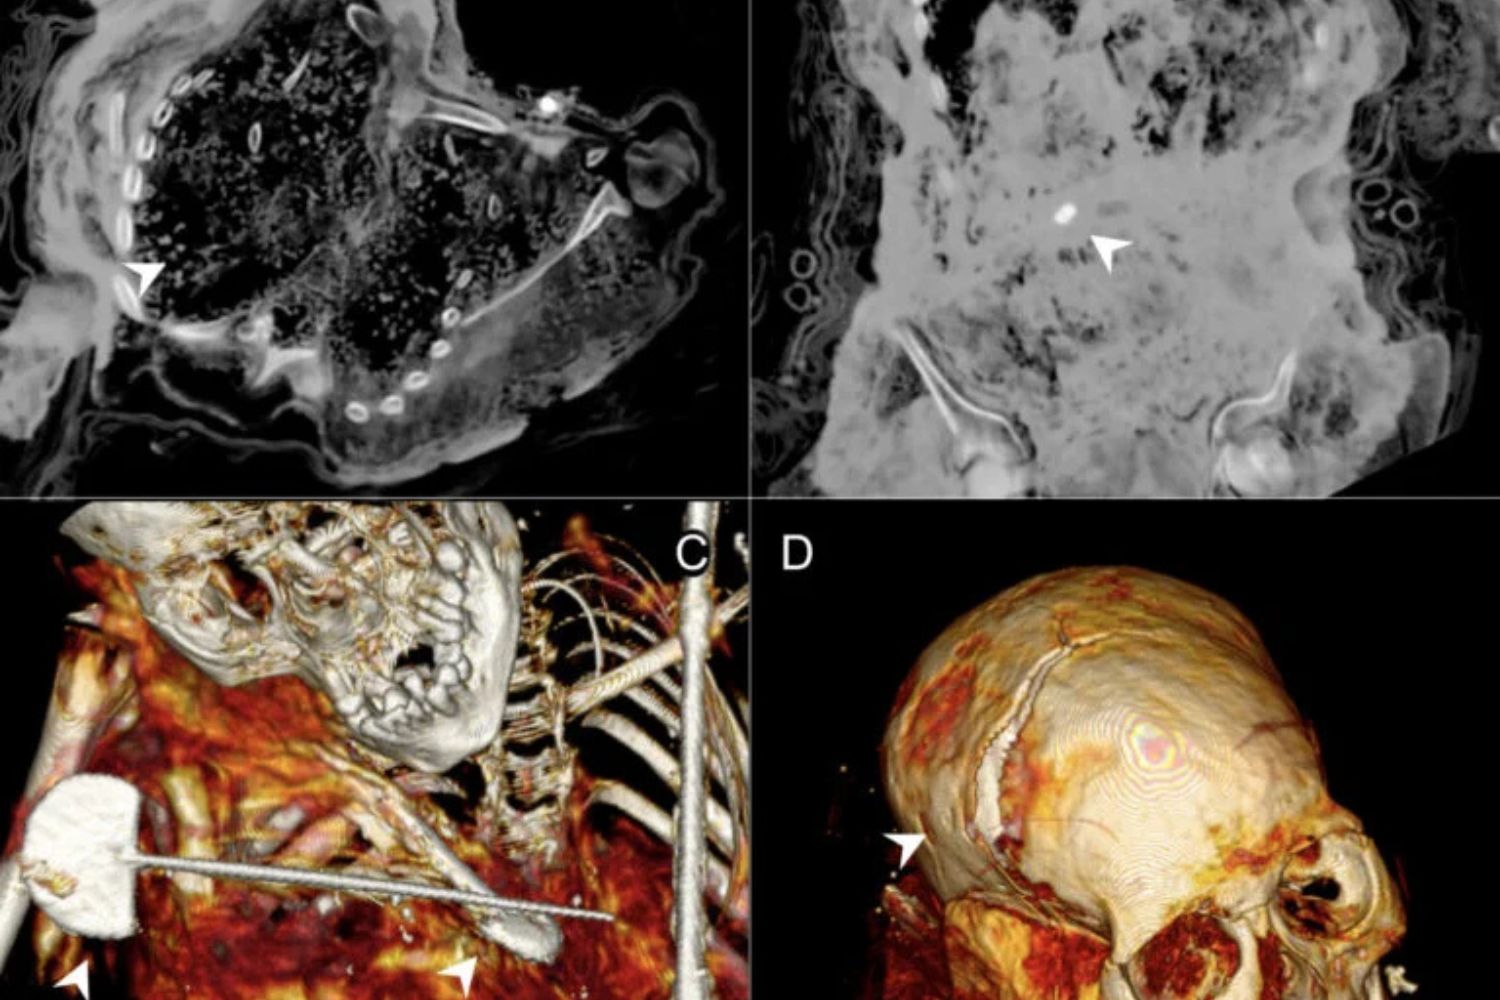

El escaneo computarizado de Ampato 1, conocida como la Doncella de Ampato, reveló lesiones en su cráneo, en su pelvis y en el pecho. El trauma en la cabeza y la pelvis habría resultado fatal. Murió aproximadamente con 14 años y su cuerpo se momificó naturalmente debido a las temperaturas extremadamente bajas. Sus restos se descubrieron junto con bolsitas que contenían maíz, y también había fragmentos de cerámica y estatuillas.

La niña identificada como Ampato 2 murió cuando tendría unos ocho años, también debido a una terrible lesión en la cabeza. Los análisis de la tomografía sugieren que tenía problemas de salud de larga data, y eso contradice los textos históricos que indican el tipo de niños seleccionados para los sacrificios.

La niña de unos 10 años a la que llamaron Ampato 4 murió (sí, adivinaste) por una lesión fatal en la cabeza. También ella reveló algo sorprendente: parece que modificaron intencionalmente su cuerpo después de su muerte, y que tal vez la sepultaron dos veces. El equipo identificó rocas y retazos textiles en su cavidad abdominal, y vieron que además faltaban algunos huesos. Por eso Ampato 4 es la primera víctima del capacocha que se sepa hasta hoy que fue momificada deliberadamente.

En cuanto a la momia Sara Sara, era una niña de unos 14 años, y sus lesiones craneales son similares a las de Ampato 1, lo que significa que probablemente también fue víctima del ritual capacocha. Sus restos se momificaron naturalmente, y revelaron que tenía problemas de salud similares a las de Ampato 2.